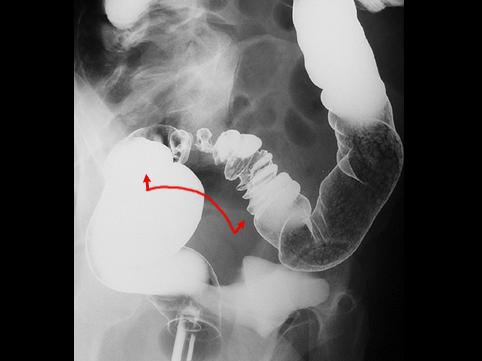

疾患(病理主体)の分類腫瘍様病変/子宮内膜症

部位(臓器別)大腸/S状

検査方法X-P

病変の最大径(ミリ)40以上